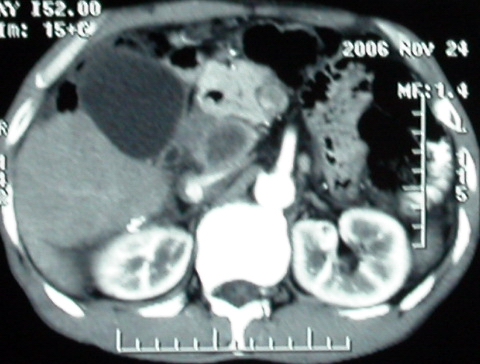

增强ct所见

影像表现:胆囊扩张、肝内胆管不扩张,且见肝脏内树枝样气体影;十二指肠后方等密度占位,中心有不规则囊变区。增强实质部分轻度强化。下部腔静脉未强化------有栓子吗?

ct表现:1,胰腺钩突后方肿块,不均强化,中心密度低,钩突及门静脉前移。2:肝右后叶不均强化灶,突出肝表面,3:胆囊明显增大,肝内胆管及肝总管内积气。4:腹腔内少量积液。

补充一点重要资料:今日查afp大于正常值10倍以上。因此,本病例最大可能应该是肝癌。

肝脏尾状叶肝癌(沿肝十二指肠韧带向下韧带内生长,门腔间隙外压增大),大结节性肝硬化,胆囊积脓,胆道感染。术中见肝外胆道2cm直径,肿瘤向前压迫胆管至扁平状态。